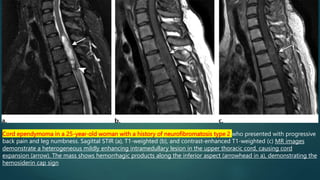

• widened spinal cord (as ependymomas arise from ependymal cells lining the central canal, they tend to occupy the central portion of

the spinal cord and cause symmetric cord expansion)

• Non-tumoral cysts are present in 62% 5

• Surrounding cord odema

• large lesions may cause scalloping of the posterior vertebral bodies and neural exit foraminal enlargement

Cord ependymoma in a 25-year-old woman with a history of neurofibromatosis type 2 who presented with progressive

back pain and leg numbness. Sagittal STIR (a), T1-weighted (b), and contrast-enhanced T1-weighted (c) MR images

demonstrate a heterogeneous mildly enhancing intramedullary lesion in the upper thoracic cord, causing cord

expansion (arrow). The mass shows hemorrhagic products along the inferior aspect (arrowhead in a), demonstrating the

hemosiderin cap sign